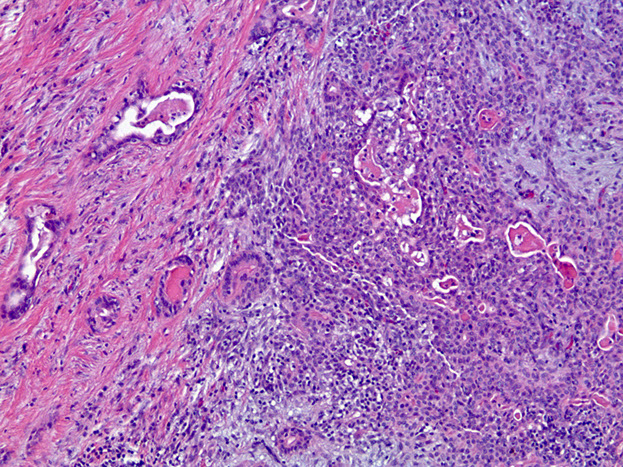

Adenoid Cystic Carcinoma

- aka cylindroma

~1/15 of all salivary gland tumors; seen in older women

- mostly (60%) seen in minor salivary glands, esp in the palate; (MC malignant tumor of minor salivary glands)

Have extensively invasive growth patterns, esp perineural invasion

Micro: Biphasic c ductal lining and ME cells with cribriform, tubular or solid pattern and hyaline material filling the spaces bwt tumors (stromal hyalinization [thick BM])

- usually contains at least some cribriform nests (Swiss cheese) filled c myxoid (blue goo), but may not be present on small bx

- tumor cells should not have intracytoplasmic mucin (found in MEC) - mucin is secreted into pseudocysts - also shound not have squamous metaplasia

- considered high-grade if >30% has solid growth pattern - has calcification / comedonecrosis in high grade

Genes: LOH at 6q23-35, MYB-NFIB in 1/2

IHC: (+) ME pos for CK (lumen epithelial cells) / p63 (basal-myoepithelial cells) / calponin / SMA / S100 / GFAP, epithelium pos for CK/EMA/CEA/c-kit (luminal) and CD117???

DDx: PLGA (PLGA has less mits, less hyperchromasia, less dense fibrous stroma, smaller nests and less nuclear polymorphism); PA

Tx: Radical excision and rads

Px: Tend to recur and met; thus are high risk and have relatively low 5- and 10-year survivals (MC mets to lung)

- high tendency for perineural invasion

Adenoid cystic ca

High grade adenoid cystic ca c comedo necrosis